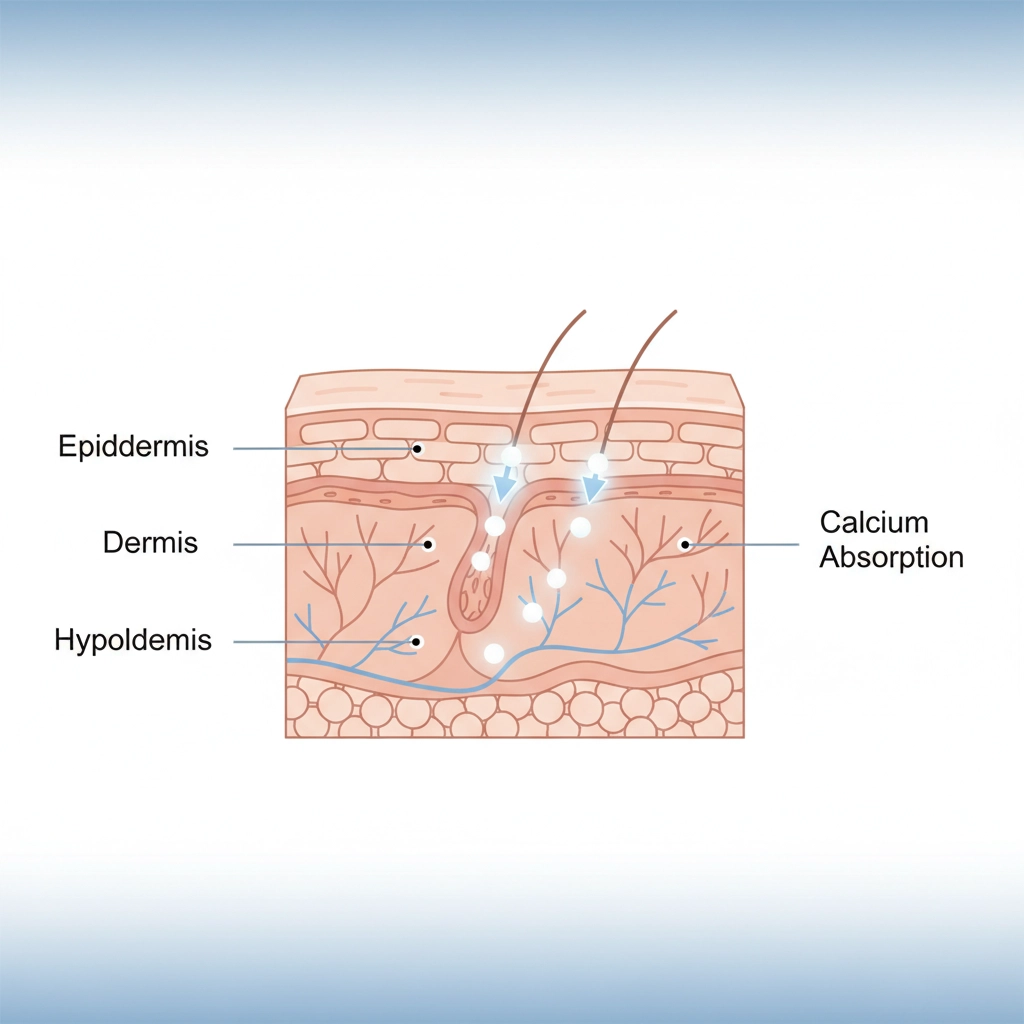

What makes Clayer different? Our French Green Clay contains over 75 trace minerals that work synergistically to:

✅ REDUCE INFLAMMATION at the cellular level

✅ ACCELERATE TISSUE REPAIR through enhanced mineral absorption

✅ IMPROVE CIRCULATION instead of restricting it

✅ ELIMINATE TOXINS that slow recovery

- Delivers essential minerals to injury site

- Supports cellular regeneration